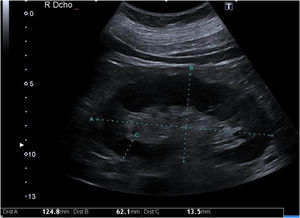

Grosor parenquimatoso, grosor cortical y ancho renalExiste correlación del grosor parenquimatoso con el grado de ERC mejorando estadísticamente esta asociación si se corrige por altura corporal1. Se ha asociado inversamente con el grado de atrofia tubular. Sin embargo, no es así con el espesor cortical11 (fig. 1).

El espesor parenquimatoso corregido fue el único parámetro de modo B (excluido la ecogenicidad parenquimatosa) que se redujo de forma progresiva conforme disminuía el FGe. Este parámetro demostró tener mayor especificidad según la curva ROC para distinguir un FGe inferior a 60mL/min comparado con las curvas ROC de la longitud, cortical y ancho renal. Sin embargo, presentó un área bajo la curva (AUC) inferior en comparación con la ecogenicidad del parénquima renal1,12.

El parámetro del grosor de la corteza renal es poco utilizado por los investigadores por la dificultad de medición en pacientes con mala diferenciación coticomedular, hallazgo que se observa más frecuentemente en paciente con ERC avanzada. Al presentar una interfaz difícil de identificar, la reproductibilidad es baja, por este motivo pocos estudios lo utilizan y esto se traduce en que no haya datos consistentes acerca de la asociación de grosor de la corteza renal y deterioro de función renal. Asimismo, Beland et al.13 demostraron que el grosor de la cortical estaba estrechamente correlacionado con el FGe (fig. 2).

Por lo descrito anteriormente, los estudios encuentran que los parámetros que mejor se correlacionan con el FGe son la longitud renal y espesor parenquimatoso corregido por la altura corporal y peso1,12.